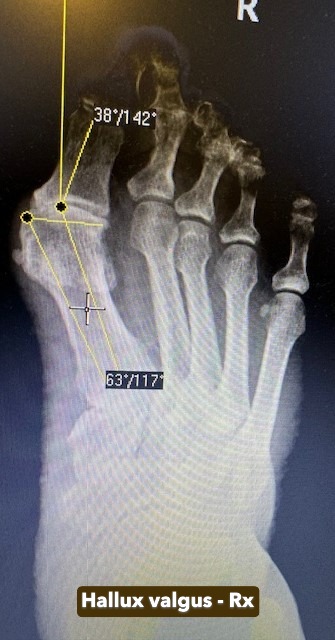

Hallux Valgus

Hallux valgus este o deformare a antepiciorului caracterizată prin devierea laterală a degetului mare și proeminența articulației de la baza acestuia („montul”). Afecțiunea apare frecvent la femei și este favorizată de încălțămintea strâmtă sau tocurile înalte. Poate provoca durere, inflamație și dificultăți la mers. Tratamentul variază de la măsuri conservatoare (încălțăminte adecvată, orteze) până la corecție chirurgicală.

Galerie imagini cu Hallux Valgus tratate de dr. Chitea Claudiu-Daniel